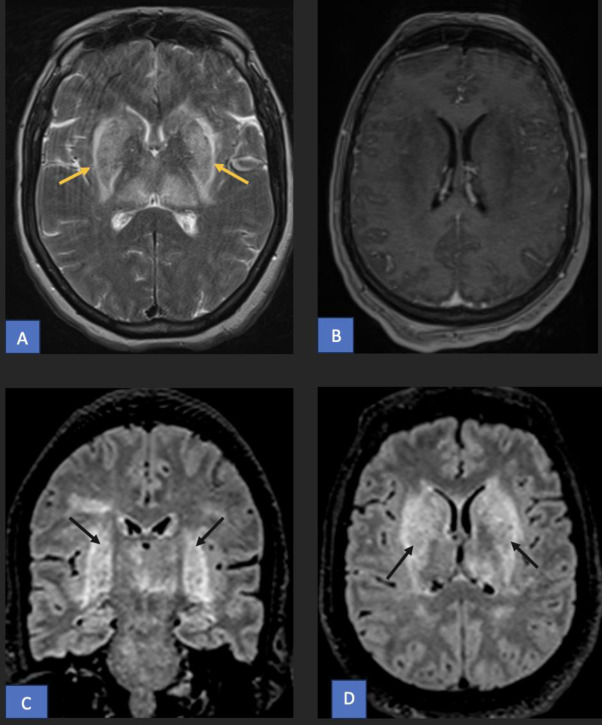

This is a 60-year-old woman with a history of ischemic stroke 5 years ago, previously presenting with aphasia and right-sided weakness, with complete recovery. She now presents with recurrent aphasia and right-sided weakness. In the ED, she was found to have a urinary tract infection with sepsis. MRI brain DWI showed no new diffusion restriction. After 2 days of antibiotics, her neurological deficits completely resolved. Question: What do you see on the MRI? How do you explain her recurrent aphasia and right-sided deficits despite no new imaging changes? #Neuroradiology #Neurology #Stroke #UTI #FOAMed